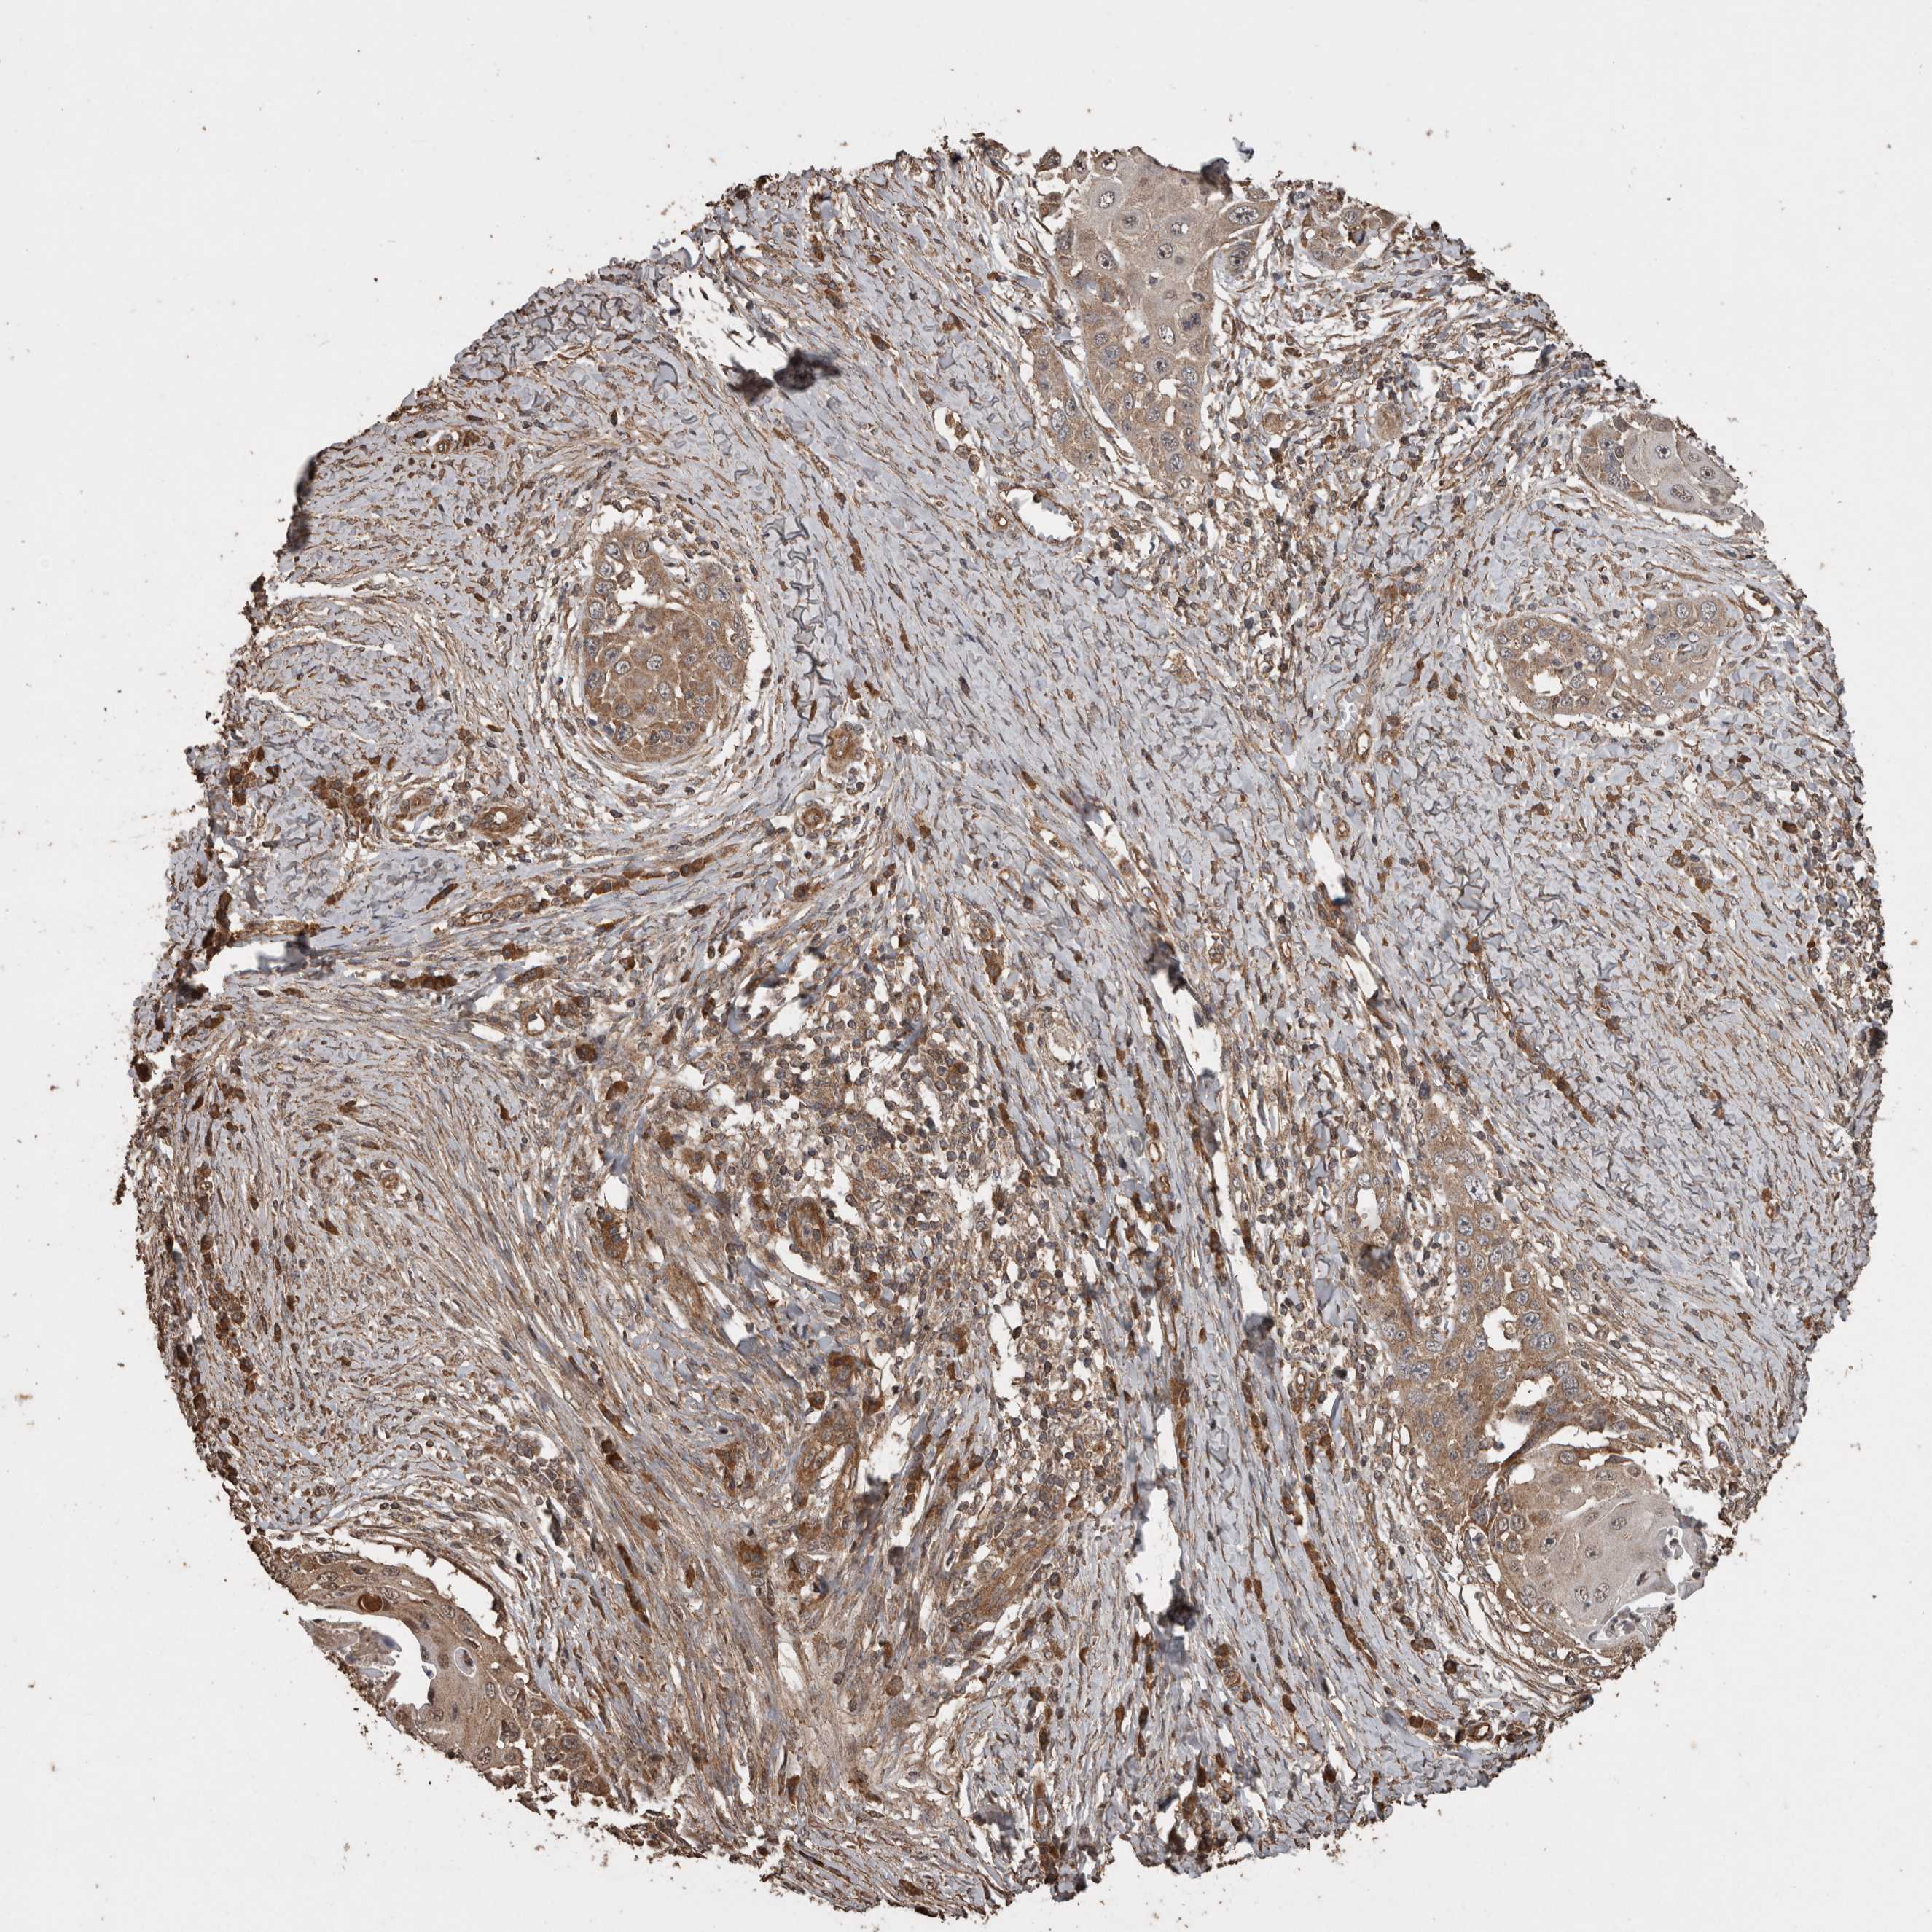

SKIN CANCER - Protein expressioni

A mouse-over function shows sample information and annotation data. Click on an image to view it in a full screen mode. Samples can be filtered based on level of antibody staining by selecting one or several of the following categories: high, medium, low and not detected. The assay and annotation is described here.

Each image is clickable and will lead to virtual microscopy that enables deeper exploration of all samples and also displays staining intensity scores, fraction scores and subcellular localization as well as patient and tissue information for each sample.

Antibody HPA001931

Squamous cell carcinoma, NOS